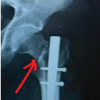

Out of 138 fractures, 107 (77.5%) achieved union, whereas 31 (22.5%) resulted in non-union. Univariate analysis revealed that the Gustilo-Anderson grade, treatment modality, time lag to treatment, and presence of diabetes mellitus were significantly associated with non-union. The non-union rate increased progressively with higher Gustilo-Anderson Grades – 3.3% in Grade I, 20% in Grade II, 54.8% in Grade IIIA, and 66.7% in Grade IIIB (P < 0.001). The type of treatment also had a significant impact, with nailing showing the lowest non-union rate (8.5%), while Ilizarov (66.7%) and LRS (41.7%) had higher rates (P < 0.001) (Graph 6 ).

Graph 6: Showing types of treatment.